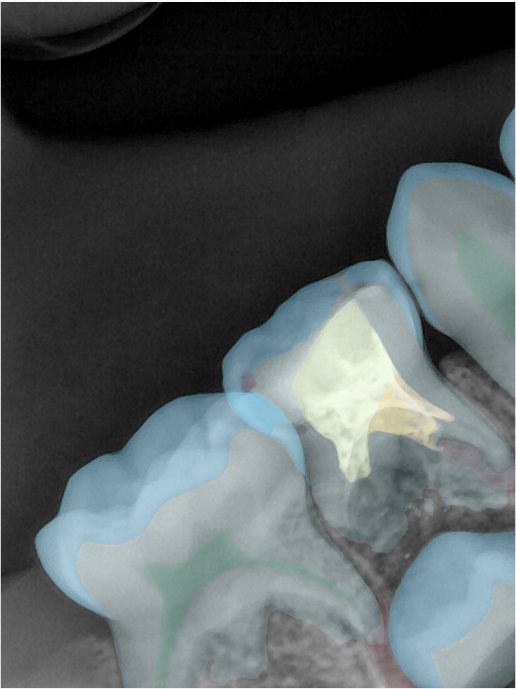

CR/DR 牙齿分割阶段记录

当前进展

- 完成了 CR/DR 牙齿相关分割训练

- 当前结果已经达到阶段预期,但仍有细节问题需要继续处理

相关测试

遇到的问题

- 训练过程中出现过 mask 下移问题

- 部分结果会出现 box 填充异常

- mask 边缘仍然有比较明显的锯齿感

参考

第二版算法问题测试